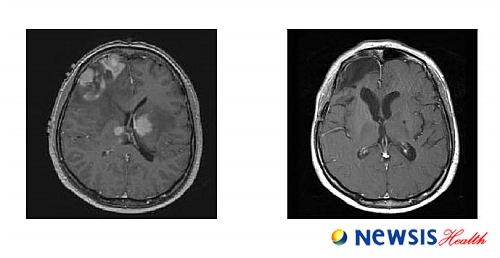

이번 연구는 2000년~2005년 16명의 원발성 뇌림프종 환자에게 국내 최초로 고용량 메토트렉세이트 요법을 적용한 것으로, 적용 환자 중 8명은 뇌종양이 완전히 사라졌고, 2명은 부분적으로 종양이 사라지는 효과를 보였다.

원발성 뇌림프종은 뇌, 척수, 안구 등 중추신경계 모든 부위에 발생돼 두통, 경련, 시력장애, 기억력장애, 인격장애 등 다양한 신경증상을 일으키는 뇌종양이다.

이 종양은 주변 뇌로 침윤이 심하고 다발성 미세침윤이 흔해서 수술만으로는 완전한 치료가 불가능하며 수술에 이어 방사선 치료를 주로 시행해 왔다.

이에 홍 교수팀은 수술 후 방사선치료 대신에 고용량 메토트렉세이트 정맥내 투여법을 우선적으로 시도했고, 이후 고용량 메토트렉세이트 요법이 효과가 없거나 재발하는 경우에 한해서만 방사선치료를 시행했다.